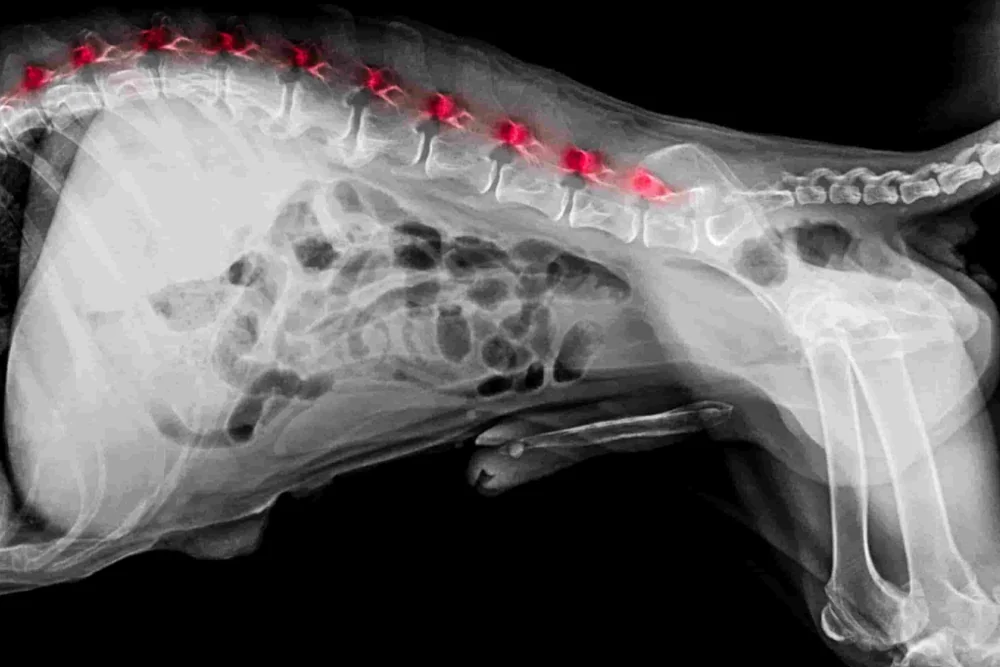

- Röntgenaufnahmen: Das Röntgenbild ist der Goldstandard bei Spondylose. Auf den Bildern sind die Veränderungen an den Wirbelkörpern meist deutlich zu erkennen. Wir sehen helle, schnabelförmige Zubildungen an der Unterseite der Wirbel, die sogenannten Spondylophyten. In weit fortgeschrittenen Fällen zeigen sich durchgehende knöcherne Brücken, welche die Wirbelzwischenräume komplett überbrücken.